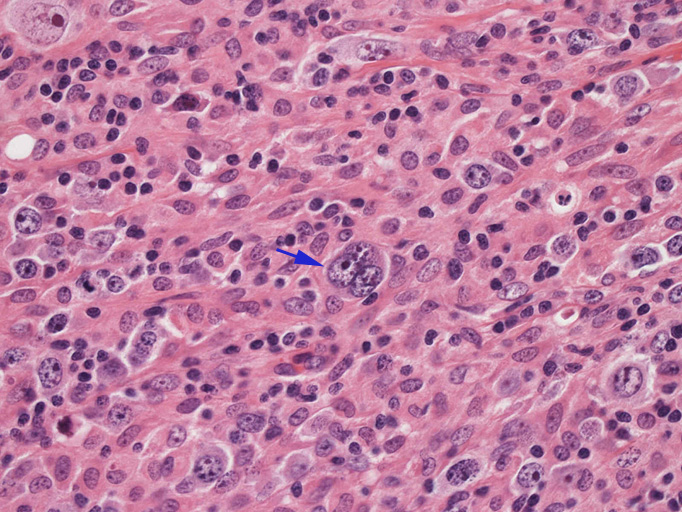

結節構造内では, 好酸性細胞質をもつ組織球の増生を背景に大型異型細胞が散在性または集蔟して増殖している。被膜下にも線維化組織内にbizzarreな大型細胞が認められる。リンパ球は小型リンパ球が大型異型細胞を含む組織球性の結節辺縁に存在する。大型細胞は, centroblastic cellが多く, その他 Hodgkin cell-like cell, RS細胞様巨細胞, 腎臓型の核をもった細胞, 多型核の細胞など多彩な形態を示す。異型核分裂像をふくむ核分裂像が多い。

- Hodgkin's cell, Reed-Sternberg細胞様大型細胞がしばしば認められる。

大型腫瘍細胞のシート状増殖はみられない。多彩な反応性背景をもちRS細胞様巨細胞が散在性に出現しホジキン病や反応性病変との鑑別が問題となる。